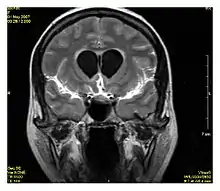

| Double inversion recovery | DIR | Simultaneous suppression of cerebrospinal fluid and white matter by two inversion times.[77] | High signal of multiple sclerosis plaques (pictured).[77] |  | |